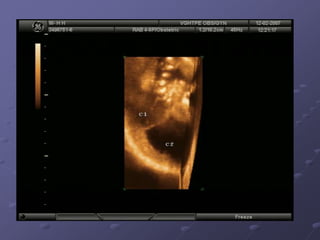

Ultrasound: An advanced ultrasound can also detect

signs of spina bifida.

Ultrasound: An advancedultrasound can also detect signs of spina bifida. Amniocentesis An analysis indicates the level of AFP present in the amniotic fluid. A small amount of AFP is normally found in amniotic fluid. when an open neural tube defect is present, the amniotic fluid contains an elevated amount of AFP because the skin surrounding the baby's spine is gone and AFP leaks into the amniotic sac. MRI